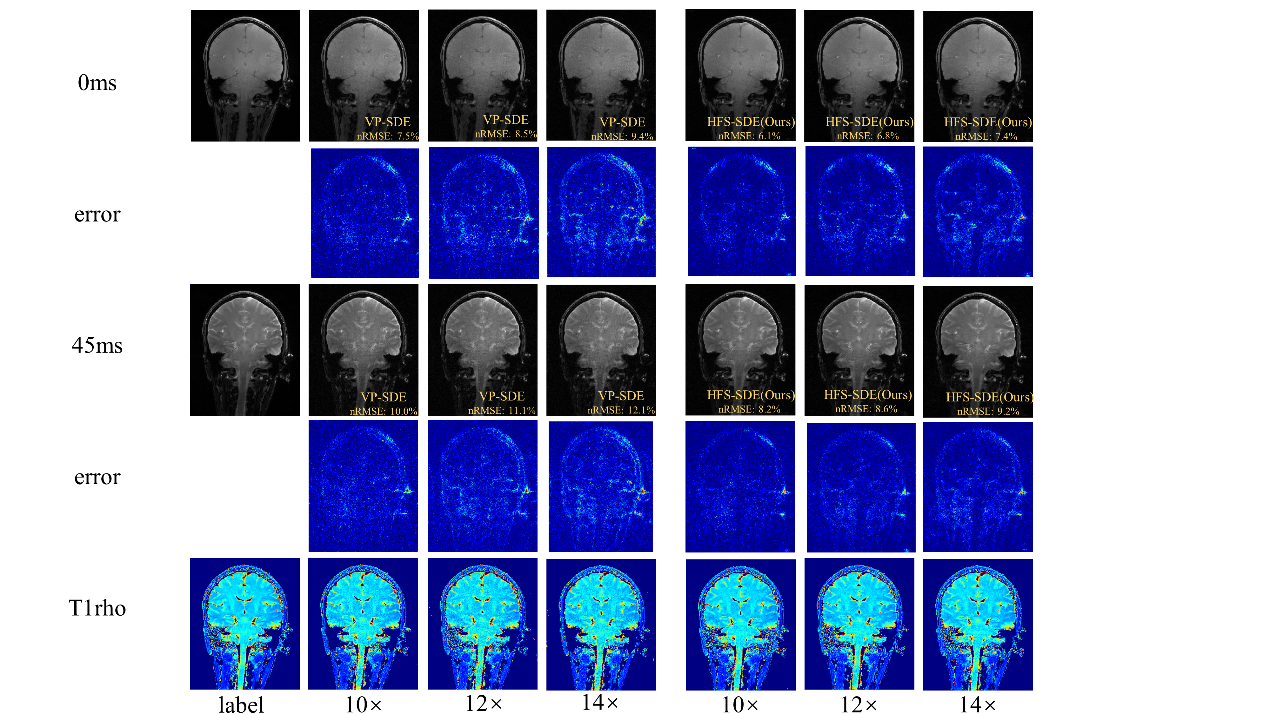

在超高场功能磁共振T1ρ弛豫定量成像方面,团队首次在5.0 T磁共振平台上测试了大脑T1ρ成像的可行性,并比较了使用3.0 T和5.0 T扫描仪所得的T1ρ值。实验结果表明,5.0T下取得了信噪比更高的T1ρ加权图像。在高分辨率成像中,5.0T的信噪比优势更明显。该成果发表在Frontiers in Physics(2022,10:1016932)。团队还提出一种用于基于扩散的MR重建方法——HFS-SDE,并将这种新方法应用于MR T1ρ映射,实现14倍的高加速度,相对于VP-SDE的高速倍数下没有显示伪影,nRMSE值明显优于VP-SDE,并且图像的高频细节得到了更好的重建,该成果“Diffusion generative prior-based highly accelerated MR T1ρ mapping”在2023 ISMRM会议被收录为Power Pitch。

图4 团队提出的HFS-SDE方法不仅提高了扩散模型的稳定性,并在5T时实现了T1ρ定量成像的高加速,而且更准确地恢复MR图像中的高频细节。